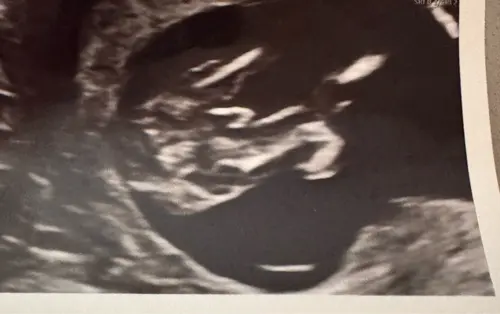

Vandaag mijn 13 weken echo gehad en de gynaecoloog kon er niet omheen. Hij ...

Dit beeld heb ik ook gezien 🤭 mijn gyno zei “we kijken deze echo niet naar het geslacht, ze hebben nu allemaal een verdikking” ja ammehoela 🤣 ik heb al een jongen dus herkende dit beeld direct 😜